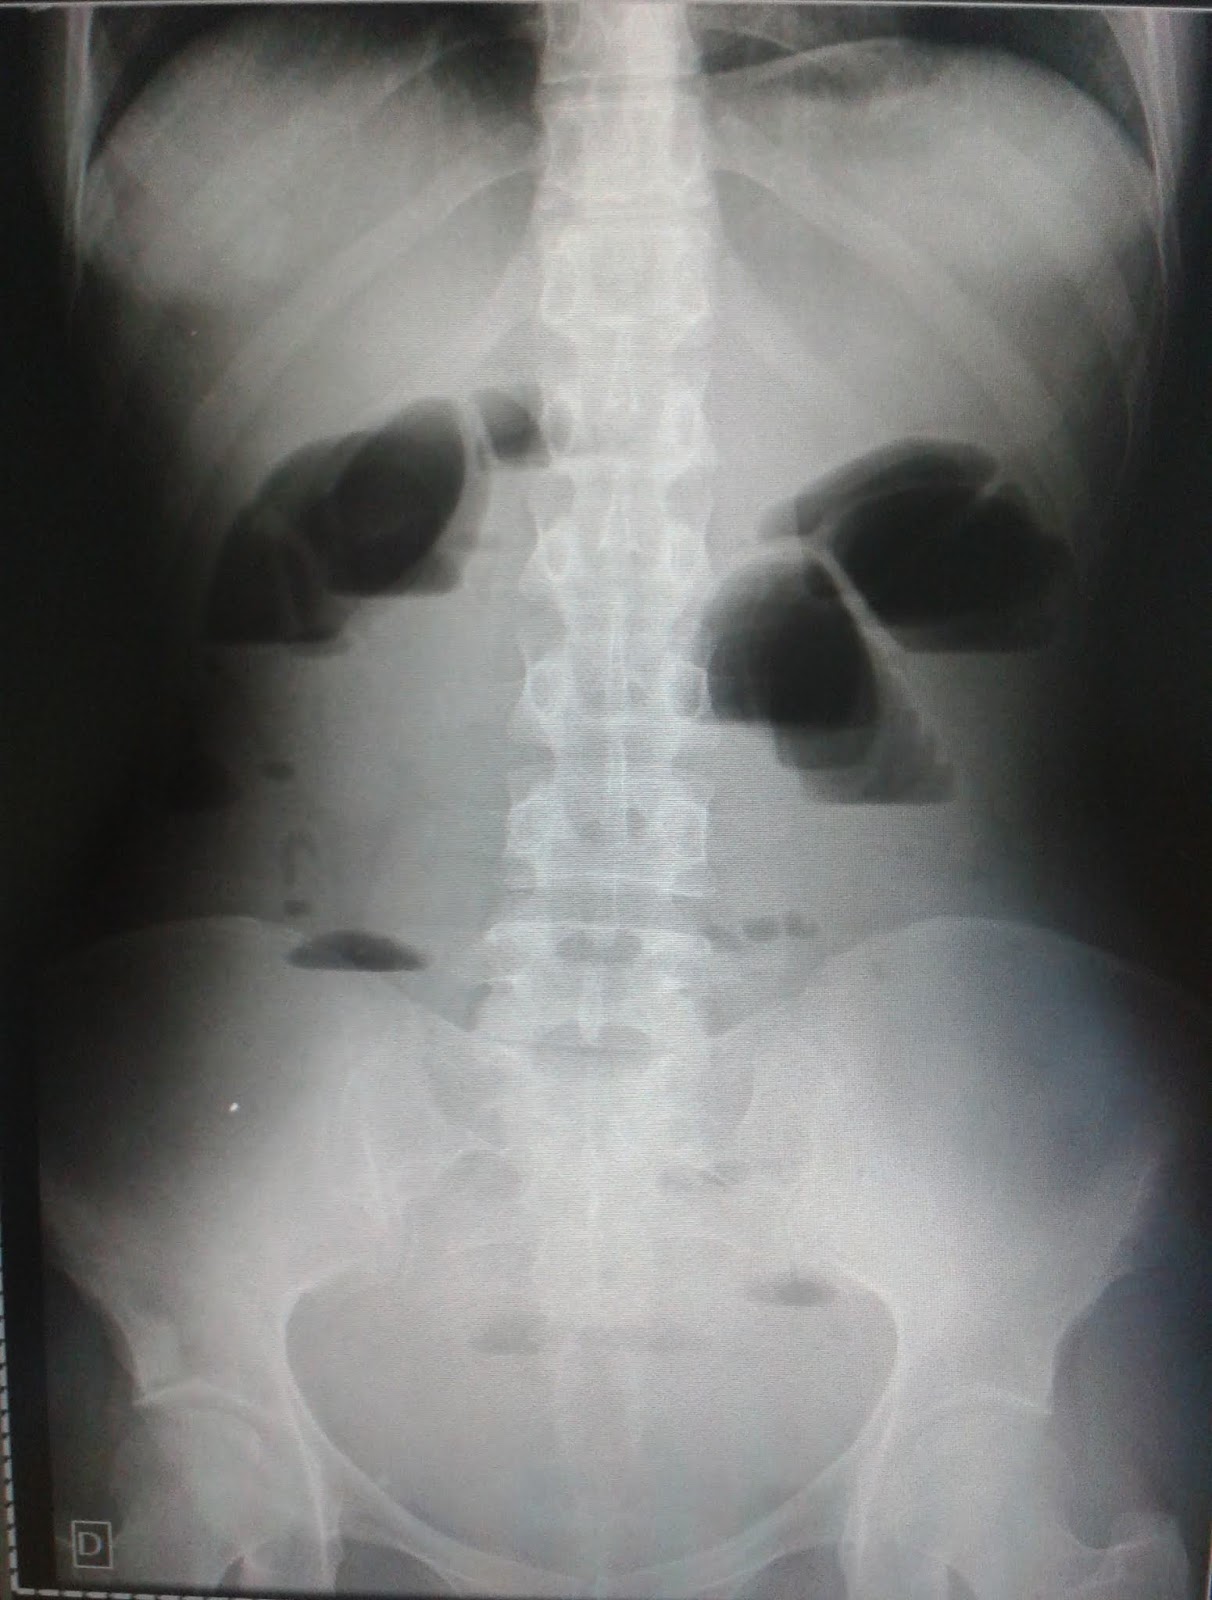

Webalthough abdominal radiography has lower sensitivity and specificity than a ct of the abdomen, it still serves a role as an adjunct or optional test. Veja a anatomia normal do. Muito utilizado devido ao baixo custo e fácil acesso, além de permitir diagnostico diferencial. Por leandro mattos | 06/07/2022. A séria de abdome agudo contém três incidências: Weba presença de calcificação no abdômen simples é sempre anormal. 90 a 95% dos cálculos urinários. Veja como é feito. O diagnóstico radiográfico é realizado com uma rotina de três incidências básicas: Webo passo a passo para a interpretação de radiografias simples de tórax e abdome que você nunca viu antes.

Weba radiografia de abdome agudo é muito importante para diagnosticar condições que necessitem de cirurgia, além de descartar casos de urgência e fazer. Websua sensibilidade é de cerca de 85% e especificidade de 90%. Assim como a tc, um exame positivo indica o início do tratamento e um resultado inconclusivo não exclui a. Webconfira tipos de radiografia e sua importância, além de informações básicas na interpretação de raio x do tórax, face, coluna e abdômen. Webobstrução intestinal é uma obstrução mecânica significativa ou bloqueio completo da passagem do conteúdo pelo intestino devido à patologia que causa o bloqueio do. Webrx normal de abdome 1) padrão de gases intestinais qualquer parte do intestino pode ser visível se contém gás / ar dentro do lúmen. Gás / ar é de baixa densidade e forma.

abdomen kub abdominal supine radiology abdo radiopaedia kidneys bladder imaging radiograph projection practice annotated

abdome raio posicionamento abdomen agudo posição abdomem ortostática pa demonstrada